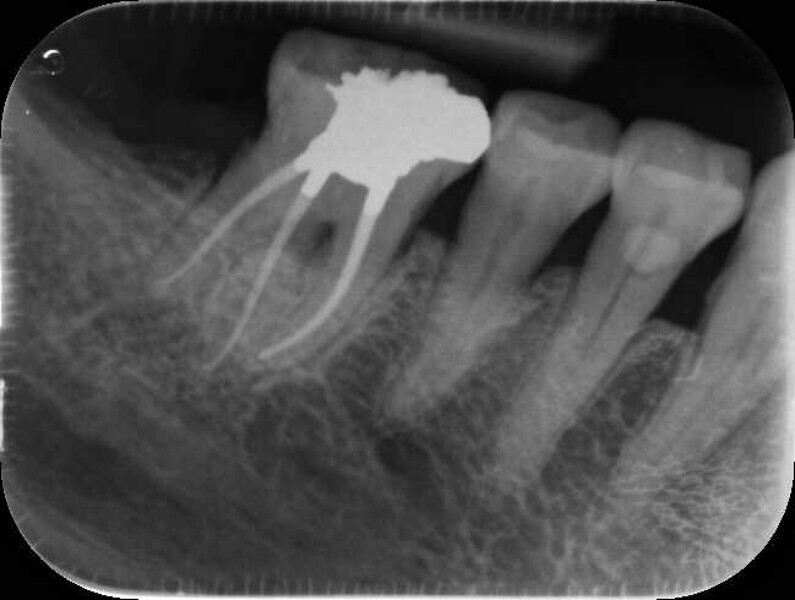

Fig. 14a: Case treated with Bassi Logic controlled memory nickel titanium files. Note the visualization of the third root on this lower molar and conservative canal preparation shape. (Courtesy of Dr. Alex Chan)

Fig. 14b: Case treated with Bassi Logic controlled memory nickel titanium files. Note the visualization of the third root on this lower molar and conservative canal preparation shape. (Courtesy of Dr. Alex Chan)